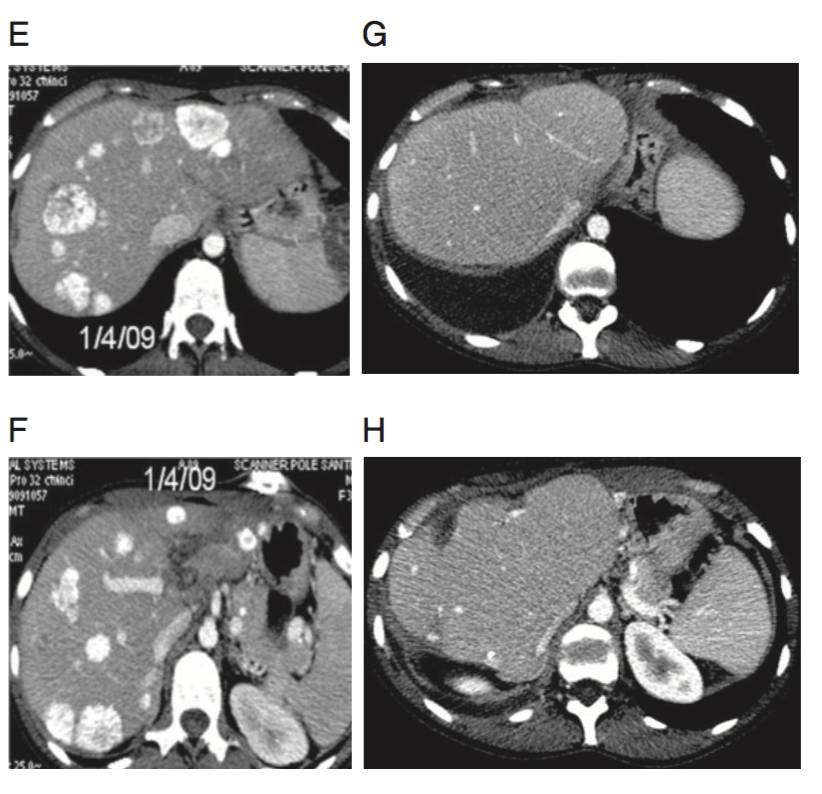

Intent-to-treat progression-free (PFS) and overall survival (OS) curves. (A) PFS and (B) OS in the 64 patients.

(C) PFS and (D) OS according to R0–R1 liver resection. Estimated 4-year survival rate according to R0–R1 resection in the ITTP: ‘yes’, 37.4% (95% confidence limit 23.7–51.1); ‘no’, 3.0% (0.0–0.6) .